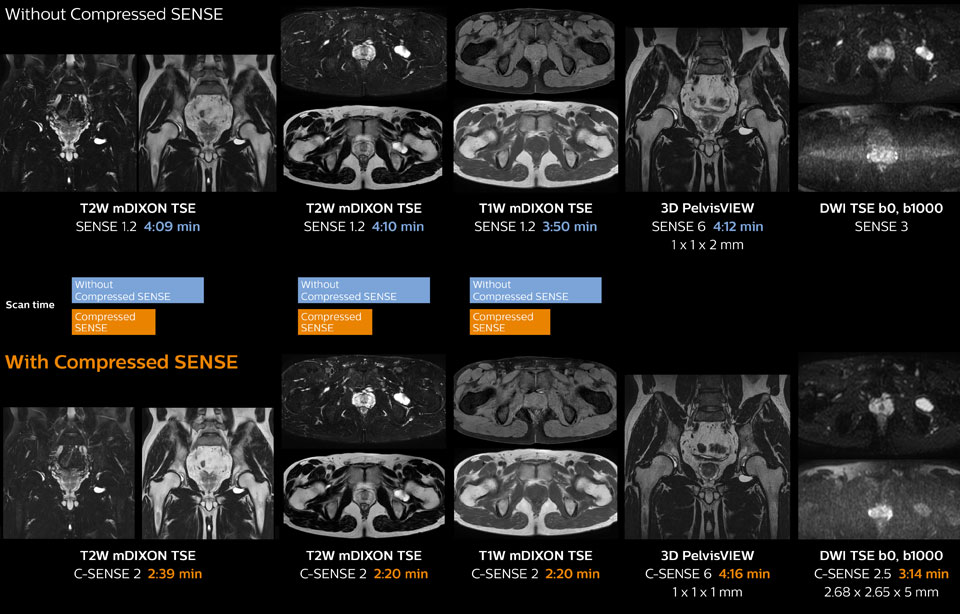

Hip with synovial cyst w/wo Compressed SENSE

Ingenia 1.5T MRI scans with and without Compressed SENSE are compared for this case of a hip with a synovial cyst. In the mDIXON sequence, the Compressed SENSE factor used is higher than the SENSE factor on the previous scan, so scan times are reduced without sacrificing image quality. The high resolution images are useful for diagnosing of a detailed dissection. The diffusion TSE with Compressed SENSE shows reduced noise compared to the Diffusion TSE with SENSE and the artifact has disappeared.

So in this case, Compressed SENSE helped in reducing scan times of the examination. The Compressed SENSE images allowed the radiologist to confidently diagnose the lesion and see the anatomic relationships of the abnormal signal to the surrounding structures.

Pelvis with myoma – comparison w/wo Compressed SENSE

In this MRI exam of pelvis in a patient with myoma, Compressed SENSE is used to accelerate individual sequences and thus the entire examination on Ingenia 1.5T.

Compressed SENSE allowed for a decrease in scan time for the T2 TSE from 3:38 to 1:46 minutes. The Compressed SENSE images in this case show fewer motion artifacts than the images from the previous protocol with SENSE.

In 3D PelvisVIEW, the Compressed SENSE images have a higher and isotropic spatial resolution with a scan time similar to the SENSE sequence. The improved spatial resolution and better contrast in the myometrium of the uterus allowed radiologist Dr. Koyama to confidently diagnose the cancerous lesion in the uterus.

The use of Compressed SENSE accelerates scanning times and increases spatial resolution in 3D PelvisVIEW.